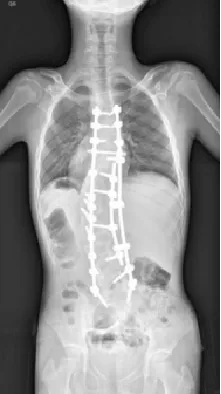

退变性脊柱侧凸是指既往无脊柱侧凸病史,发生于骨骼成熟后的脊柱畸形,常发生于脊柱侧腰段或胸腰段,多在45-50岁以后出现,女性多于男性。

▲ 女,69岁,退变性脊柱侧凸